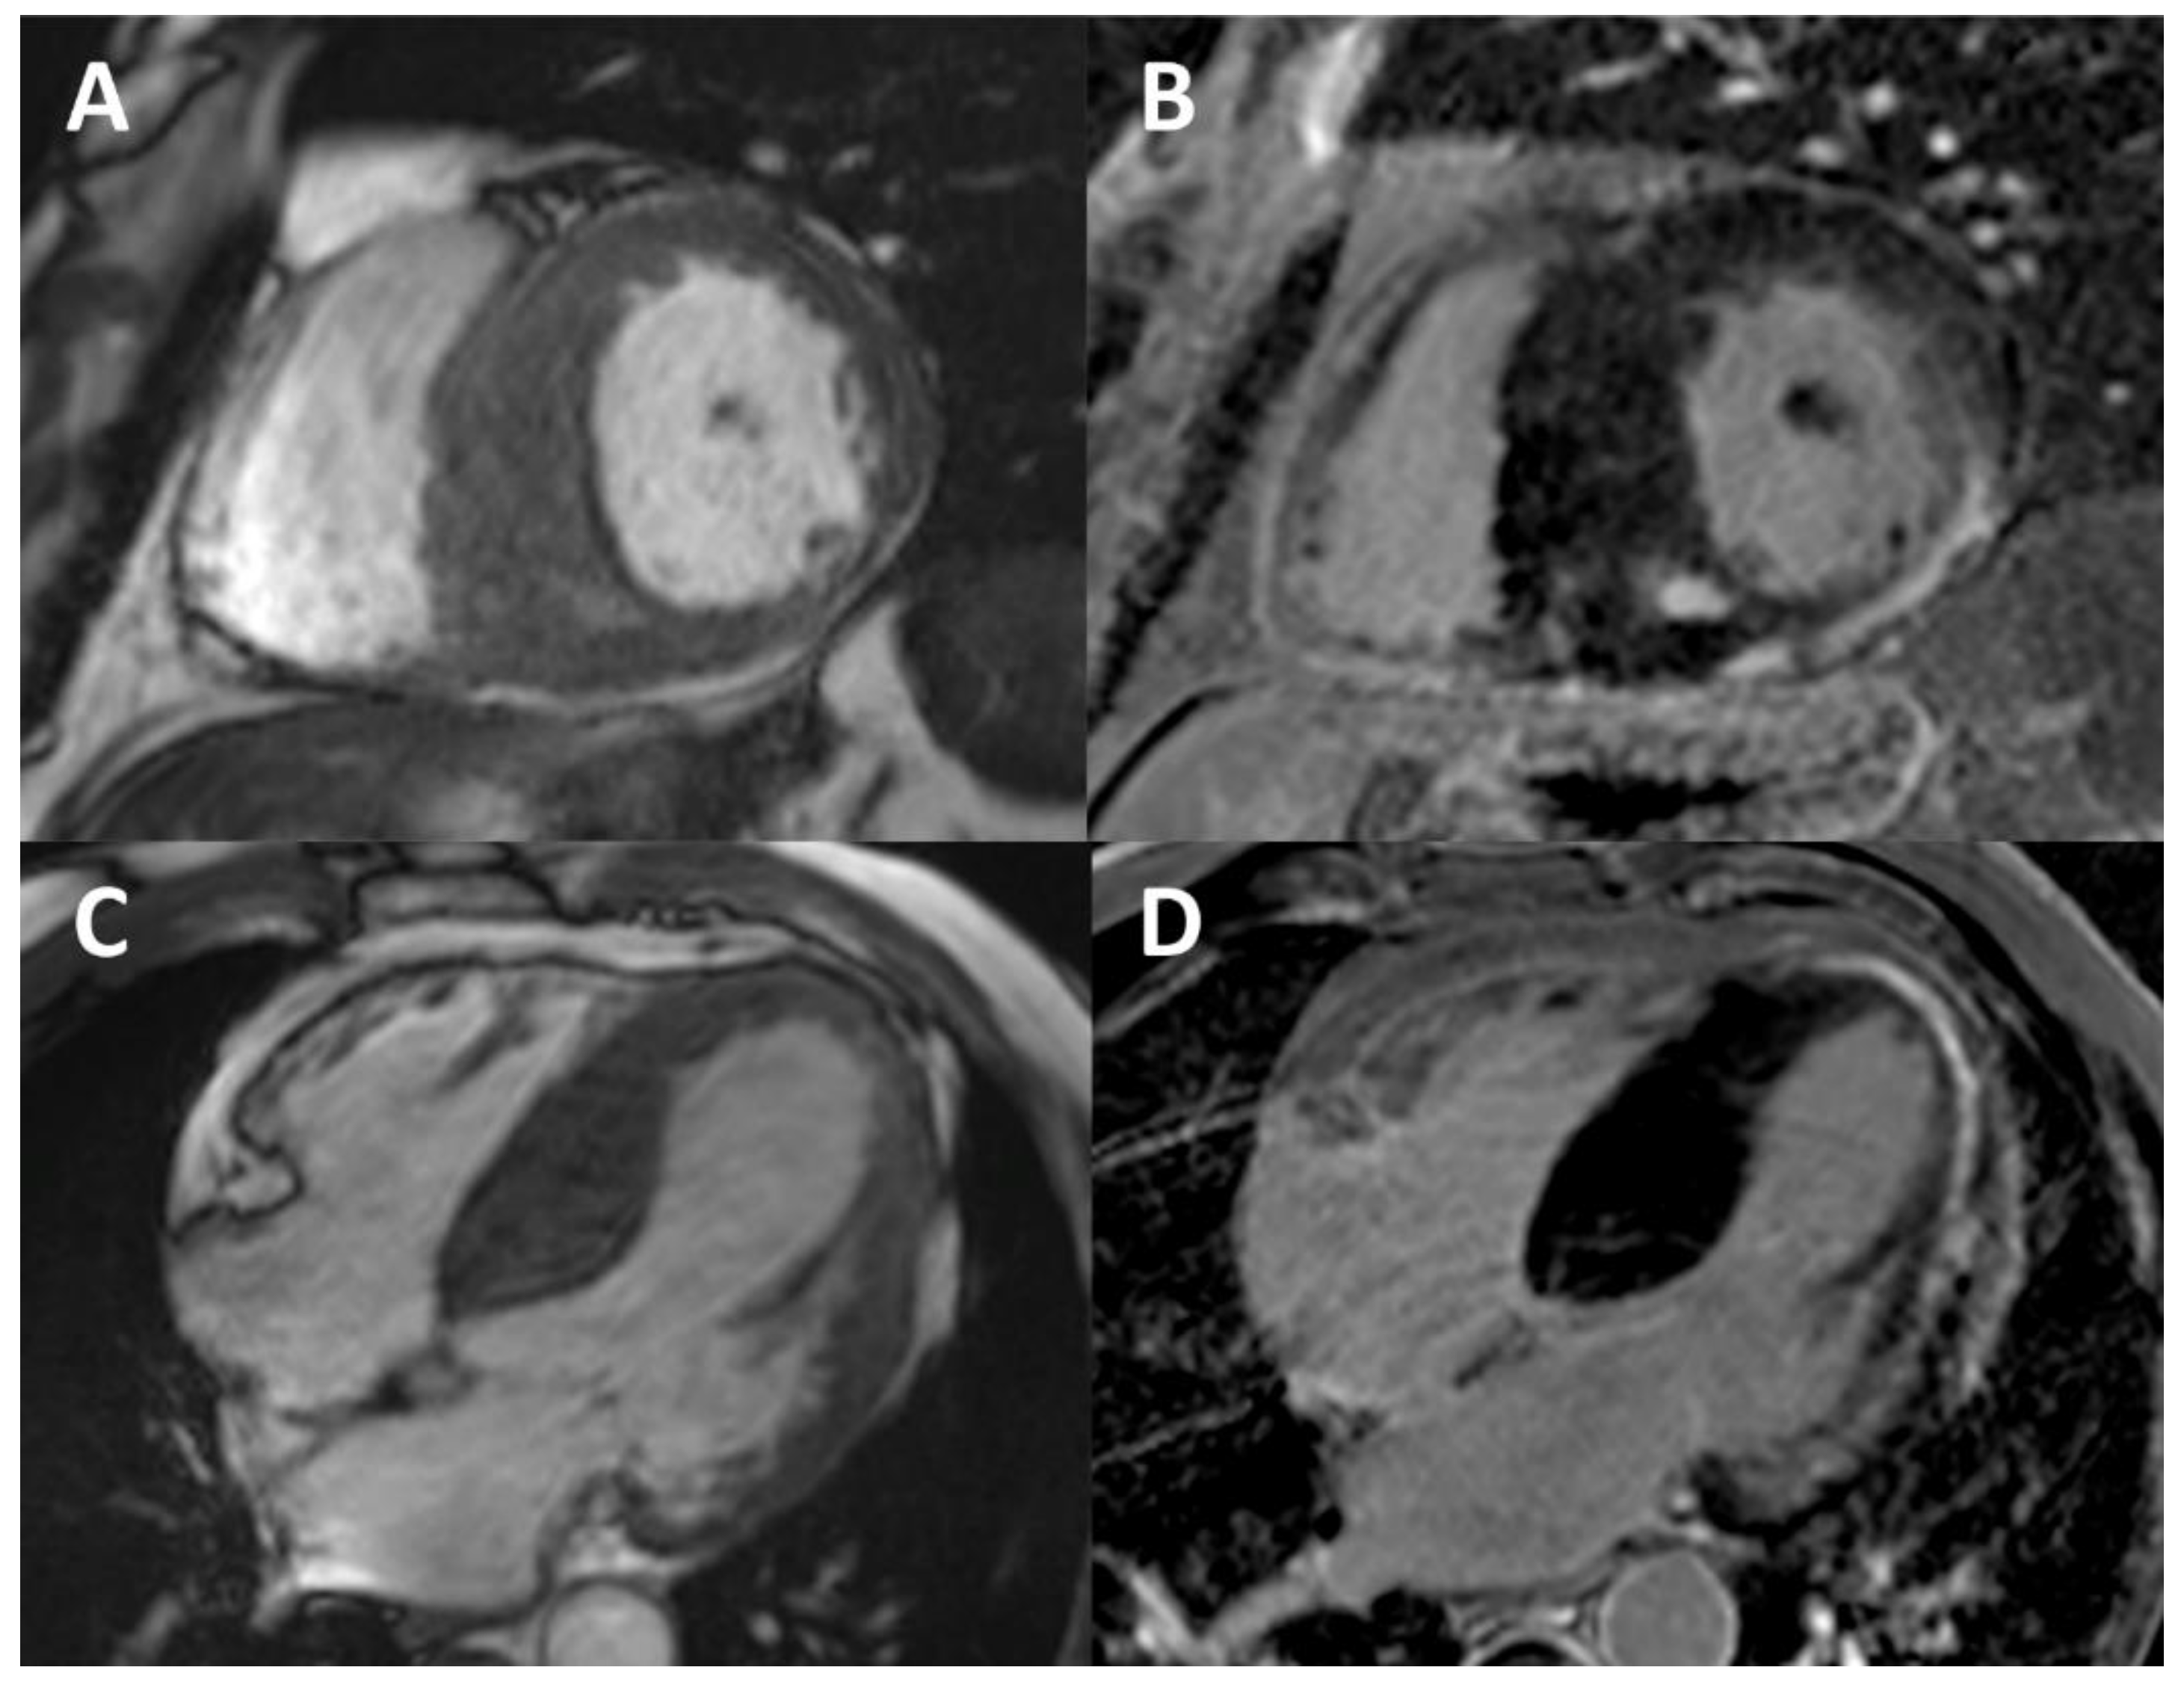

- Moon, J.C.; Sachdev, B.; Elkington, A.G.; McKenna, W.J.; Mehta, A.; Pennell, D.J.; Leed, P.J.; Elliott, P.M. Gadolinium enhanced car-diovascular magnetic resonance in Anderson-Fabry disease. Evidence for a disease specific abnormality of the myocardi-al interstitium. Eur. Heart J. 2003, 24, 2151–2155. [Google Scholar] [CrossRef]

- Moon, J.C.; Sheppard, M.; Reed, E.; Lee, P.; Elliott, P.M.; Pennell, D.J. The Histological Basis of Late Gadolinium Enhancement Cardiovascular Magnetic Resonance in a Patient with Anderson-Fabry Disease. J. Cardiovasc. Magn. Reson. 2006, 8, 479–482. [Google Scholar] [CrossRef] [PubMed]

- Deva, D.P.; Hanneman, K.; Li, Q.; Ng, M.Y.; Wasim, S.; Morel, C.; Iwanochko, R.M.; Thavendiranathan, P.; Crean, A.M. Cardiovascular magnetic resonance demonstration of the spectrum of morphological phenotypes and patterns of myocardial scarring in Anderson-Fabry disease. J. Cardiovasc. Magn. Reson. 2016, 18, 1–10. [Google Scholar] [CrossRef]

- Nordin, S.; Kozor, R.; Bulluck, H.; Castelletti, S.; Rosmini, S.; Abdel-Gadir, A.; Baig, S.; Mehta, A.; Hughes, D.; Moon, J.C. Cardiac Fabry Disease With Late Gadolinium Enhancement Is a Chronic Inflammatory Cardiomyopathy. J. Am. Coll. Cardiol. 2016, 68, 1707–1708. [Google Scholar] [CrossRef] [PubMed]

- Sado, D.M.; White, S.K.; Piechnik, S.K.; Banypersad, S.M.; Treibel, T.; Captur, G.; Fontana, M.; Maestrini, V.; Flett, A.S.; Robson, M.D.; et al. Identification and Assessment of Anderson-Fabry Disease by Cardiovascular Magnetic Resonance Noncontrast Myocardial T1 Mapping. Circ. Cardiovasc. Imaging 2013, 6, 392–398. [Google Scholar] [CrossRef] [PubMed]

- Nordin, S.; Kozor, R.; Baig, S.; Abdel-Gadir, A.; Medina-Menacho, K.; Rosmini, S.; Captur, G.; Tchan, M.; Geberhiwot, T.; Murphy, E.; et al. Cardiac Phenotype of Prehypertrophic Fabry Disease. Circ. Cardiovasc. Imaging 2018, 11, e007168. [Google Scholar] [CrossRef]

- Nordin, S.; Kozor, R.; Medina-Menacho, K.; Abdel-Gadir, A.; Baig, S.; Sado, D.M.; Lobascio, I.; Murphy, E.; Lachmann, R.H.; Mehta, A.; et al. Proposed Stages of Myocardial Phenotype Development in Fabry Disease. JACC: Cardiovasc. Imaging 2019, 12, 1673–1683. [Google Scholar] [CrossRef]